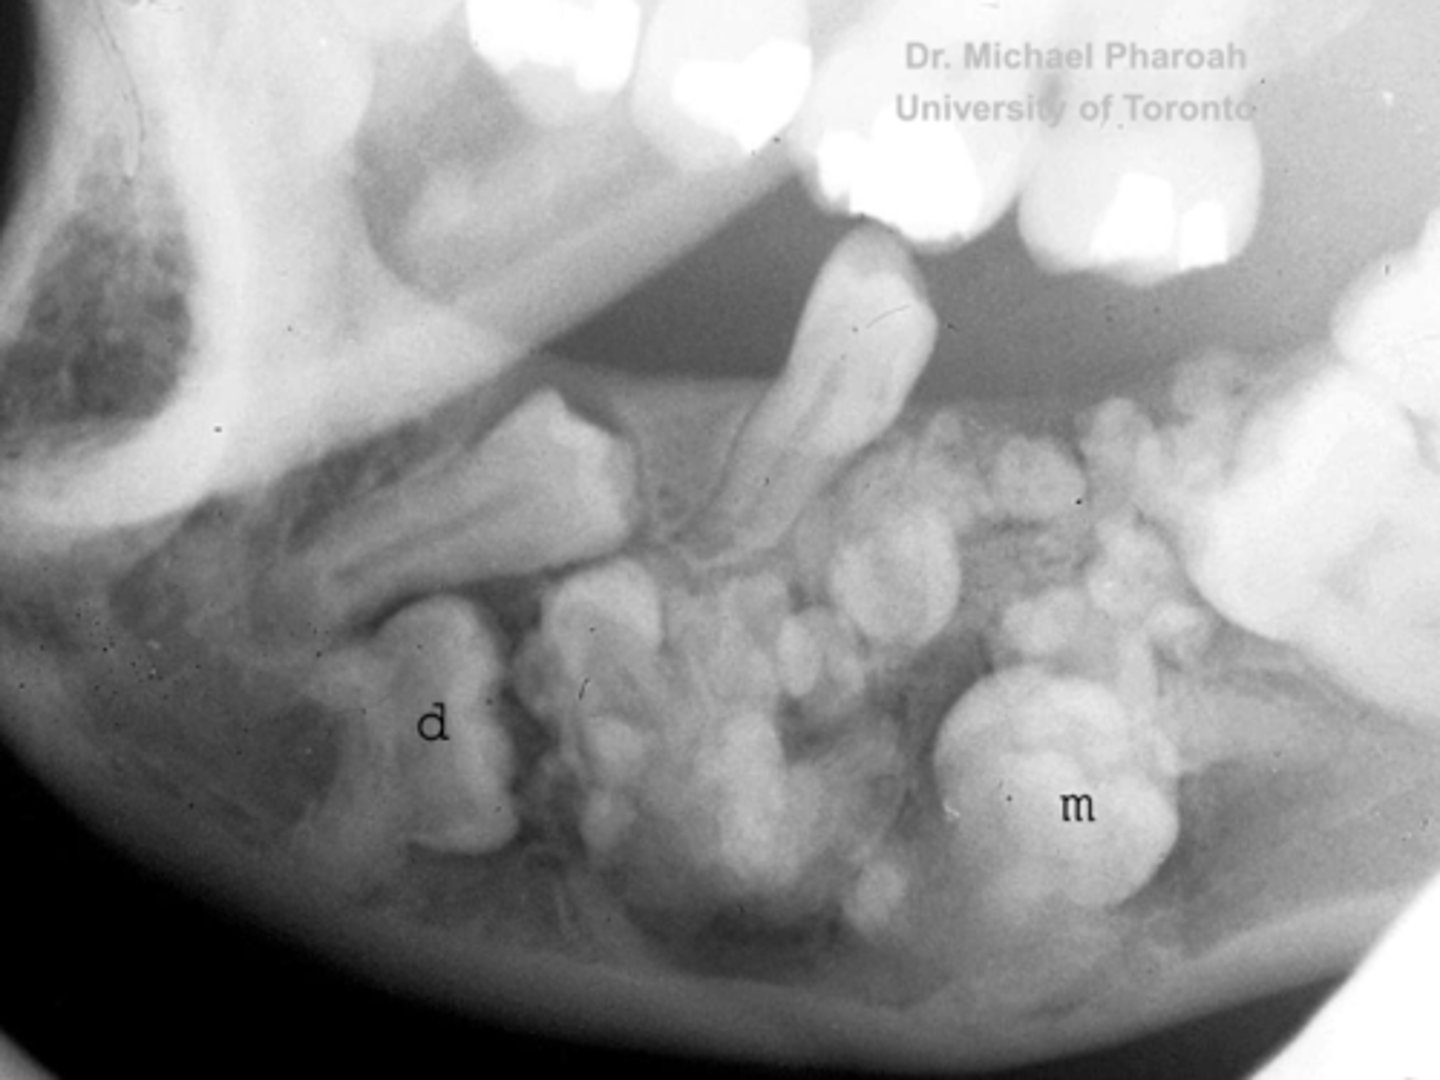

how would you describe the lesion?

A. well-defined, non corticated, periapical radiolucency associated with tooth number 14

B. ill-defined, non corticated, periapical radiolucency associated with tooth number 14

C. well-defined, corticated, pericoronal lesion with radiopaque flecks associated with an impacted tooth

D. well-defined, corticated, pericoronal radiopacity associated with an impacted tooth

What category would you put this lesion into?

Benign odontogenic tumor/cyst

all of the following could be a differential diagnosis for this lesion except?

A. AOT

B. calcifying epithelial odontogenic tumor (pindborg tumor)

C. Calcifying Epithelial odontogenic cyst (gorlin cyst)

D. osteosarcoma